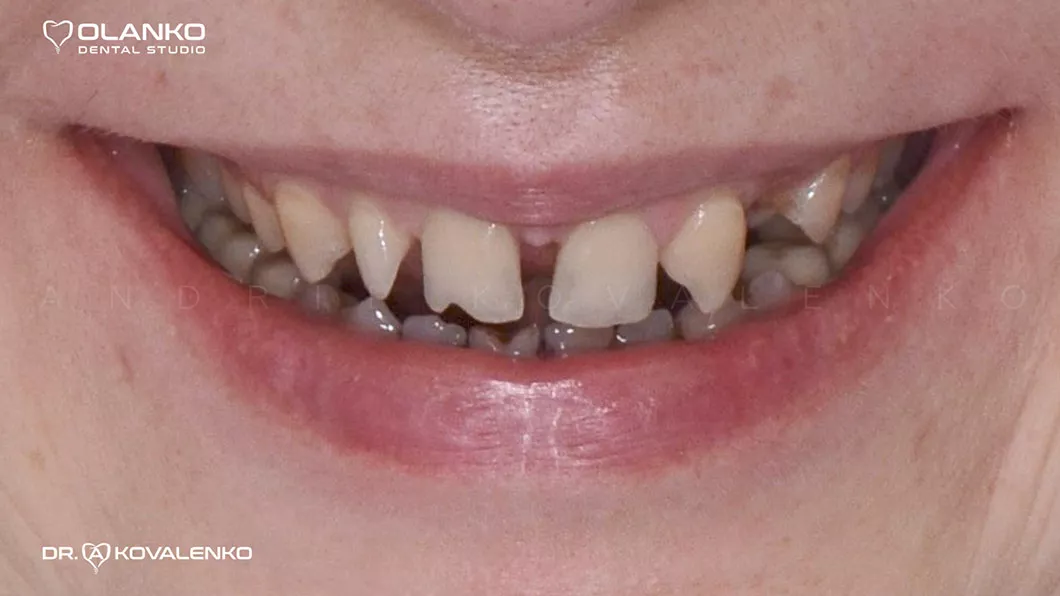

Клинический случай 3 протезирование

Пациентка обратилась с жалобами на неудовлетворительную эстетику, наличие промежутков между зубами (тремы, диастемы) полное отсутствие (адентия бокового резца слева).

Диагностика: эстетический анализ, создание проекта новой улыбки DSD (цифровой дизайн улыбки).

Проведена хирургическая коррекция десневого контура в области фронтальных зубов.

Протезирование:12 керамических реставраций (коронки,виниры на зубах и имплантате) на верхней челюсти.